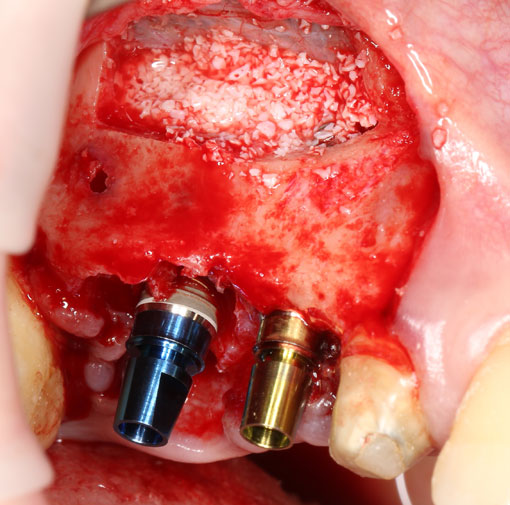

Синуслифтинг и остеопластика

В собственной клинической практике я нередко сочетаю синуслифтинг с увеличением объема альвеолярного гребня (аугментацией). Последнее может быть достигнуто методом аутотрансплантации (пересадки) костных фрагментов (рис 37, 38, 39):

Рисунок 37, 38, 39. Синуслифтинг с одномоментной аугментацией альвеолярного отростка методом аутотрансплантации костных фрагментов: слева – этап синуслифтинга, в центре – этап восстановления объема альвеолярного гребня аутокостным фрагментом, справа – установка имплантов через 3 месяца после синуслифтинга и остеопластики.

Либо комбинированной методикой с использованием барьерных мембран и остеопластических материалов (рис 40, 41, 42):

Рисунок 40, 41, 42. Синуслифтинг с одномоментной аугментацией альвеолярного отростка комбинированной методикой с использованием остеопластических материалов и барьерных мембран: слева – этап синуслифтинга, в центре – восстановление объема альвеолярного гребня с помощью остеопластических материалов, аутокостной стружки и барьерной мембраны, справа – установка имплантов через 3 месяца после синуслифтинга.